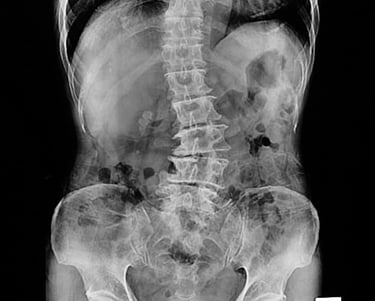

La escoliosis es una condición en la que la columna vertebral se curva de manera anormal, a menudo formando una "S" o una "C" en lugar de estar recta. Aunque algunos casos de escoliosis son leves y no causan problemas significativos, otros pueden generar dolor, incomodidad e incluso dificultar el movimiento y la postura. Comprender los síntomas, las causas y los tratamientos disponibles para la escoliosis es esencial para gestionar esta condición y mejorar la calidad de vida.

La escoliosis es una condición caracterizada por una curva anormal en la columna vertebral, que puede ocurrir a cualquier edad, pero se diagnostica comúnmente durante la niñez o la adolescencia. La curvatura puede variar desde leve hasta severa y generalmente se desarrolla a medida que la columna crece. En algunos casos, la escoliosis puede empeorar con el tiempo, lo que provoca más incomodidad, restricción de movimiento y, en casos graves, problemas respiratorios.

Aunque la causa exacta de la escoliosis generalmente se desconoce (escoliosis idiopática), existen varios tipos y causas conocidas, que incluyen: